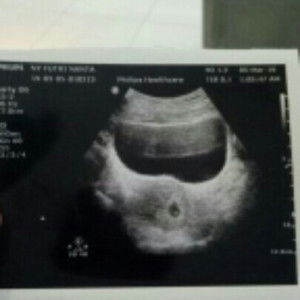

Saya memasuki kehamilan 13W dan lg sering kram. apakah menauski tm2 srg kram yah?

kalo sering kram baiknya dibawa priksa ke dokter kndungan bun.. waktu hmil dulu aku juga kram usia kandungan hmpir 5 bulan, dan ternyata kontraksi lalu dsuruh bed rest.. plus diksi suplemen dan obat lainnya..